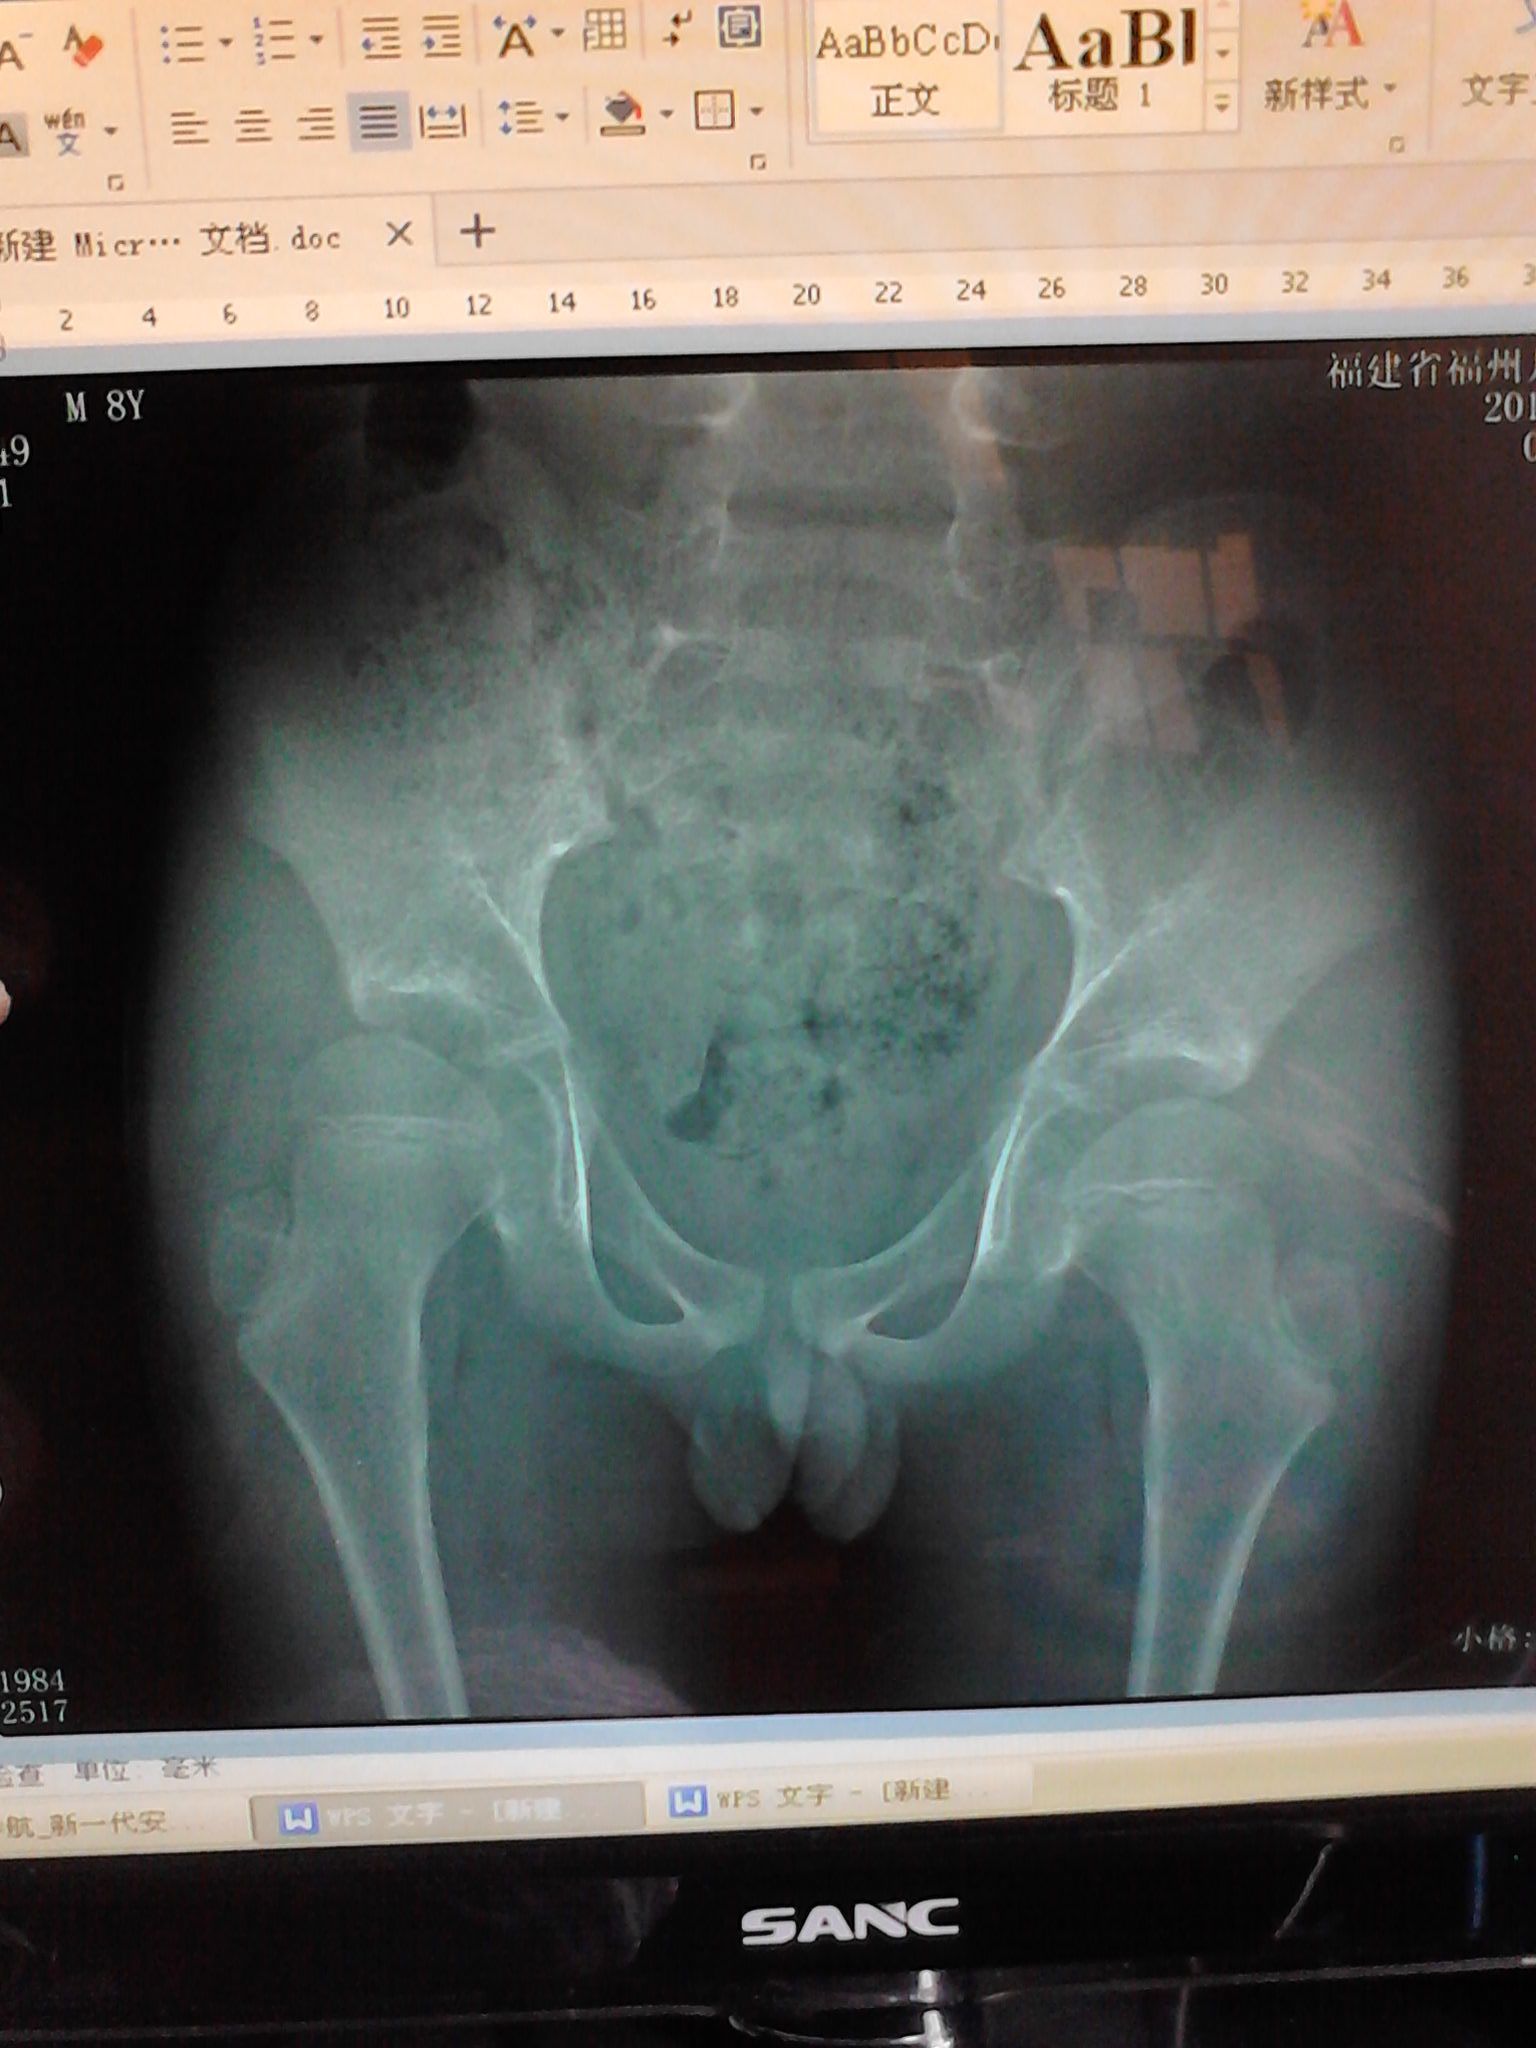

小孩9岁,男,前几天发现小孩骨膜发炎,右腿长,左腿短 后来找中医治好了,可是没过多久又出了相同的症

状,这回事右腿短,左腿长,后来去拍片才知道事情的严重性,当地医生看不出问题,后来又去市级的医院,医生仍是看不出来问题,他们说可能要动手术。想问下现在是否还可以治愈,恢复正常的样子?